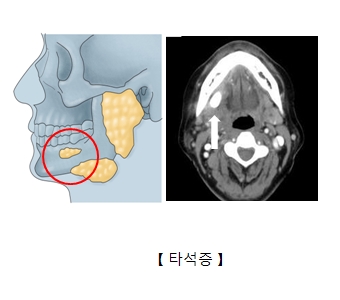

타석증의 정확한 원인은 알려지지 않았습니다. 침의 정체, 침샘관의 염증, 손상 등이 원인으로 꼽힙니다. 타석증이 주로 발생하는 부위는 턱밑 침샘인 악하선이 75%로 가장 많습니다. 그 다음은 귀밑 침샘인 이하선에서 약 20% 정도 발생합니다. 그 밖에 다른 침샘에서 5% 정도 발생합니다. 다른 부위보다 턱밑 침샘에서 타석증이 더 많이 발생하는 이유는 이곳이 귀밑 침샘에 비해 침의 정체 정도가 더 심하고 점액 함량이 더 높기 때문입니다.

타석증은 일단 시진과 촉진을 통해 통증과 부종이 있는지 진단합니다. 턱밑에 생긴 타석은 혀와 잇몸 사이를 양손으로 촉진하면 만져집니다. 그러나 타액선 내 타석은 촉진으로 진단하기 어렵습니다. 목 부분의 CT를 찍어서 뼈처럼 하얗게 보이는 타석이 있는지 관찰합니다. 타석의 크기는 모래알 크기부터 수cm까지 다양합니다. 타석의 모양도 다양합니다.